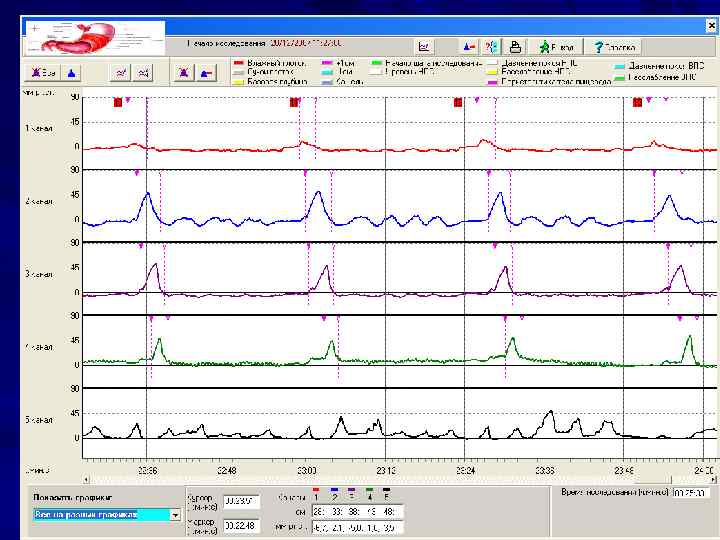

МАНОМЕТРИЯ ПИЩЕВОДА

МАНОМЕТРИЯ ПИЩЕВОДА